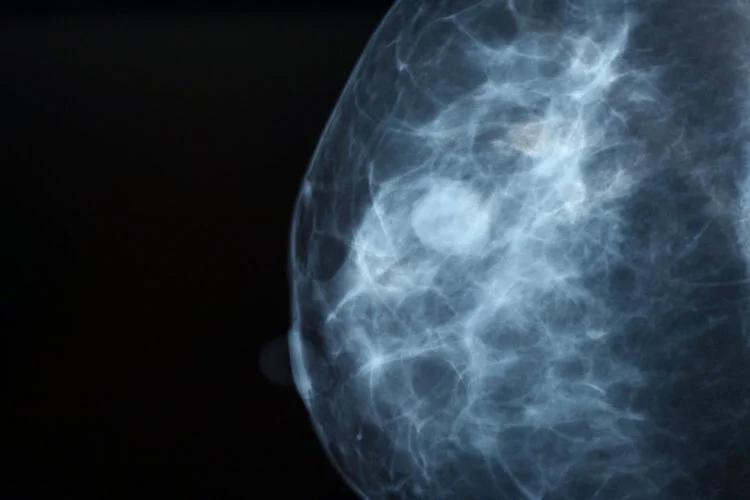

Our breast imaging has improved drastically, even over the last 10 years. A life saved is never an over-diagnosis! Mammograms are able to identify breast cancers up to two years before the patient is able to feel it and this represents an excellent intervention point. Early detection is the key to cure. Non-invasive cancer usually does not form a mass, but is still cancer and warrants appropriate treatment as well. And with the improvement of our imaging and the advent of the 3-D mammogram, we have drastically decreased patient callbacks and unnecessary biopsies.